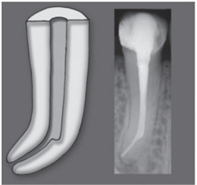

O uso das membranas em cirurgias

endodônticas através técnicas de regeneração

tecidual guiada (GTR), tem sido sugerido não

só no tratamento das perfurações radiculares

como também para o tratamento de grandes

lesões.

Considerando esta técnica, marque a alternativa que representa uma vantagem desta técnica.